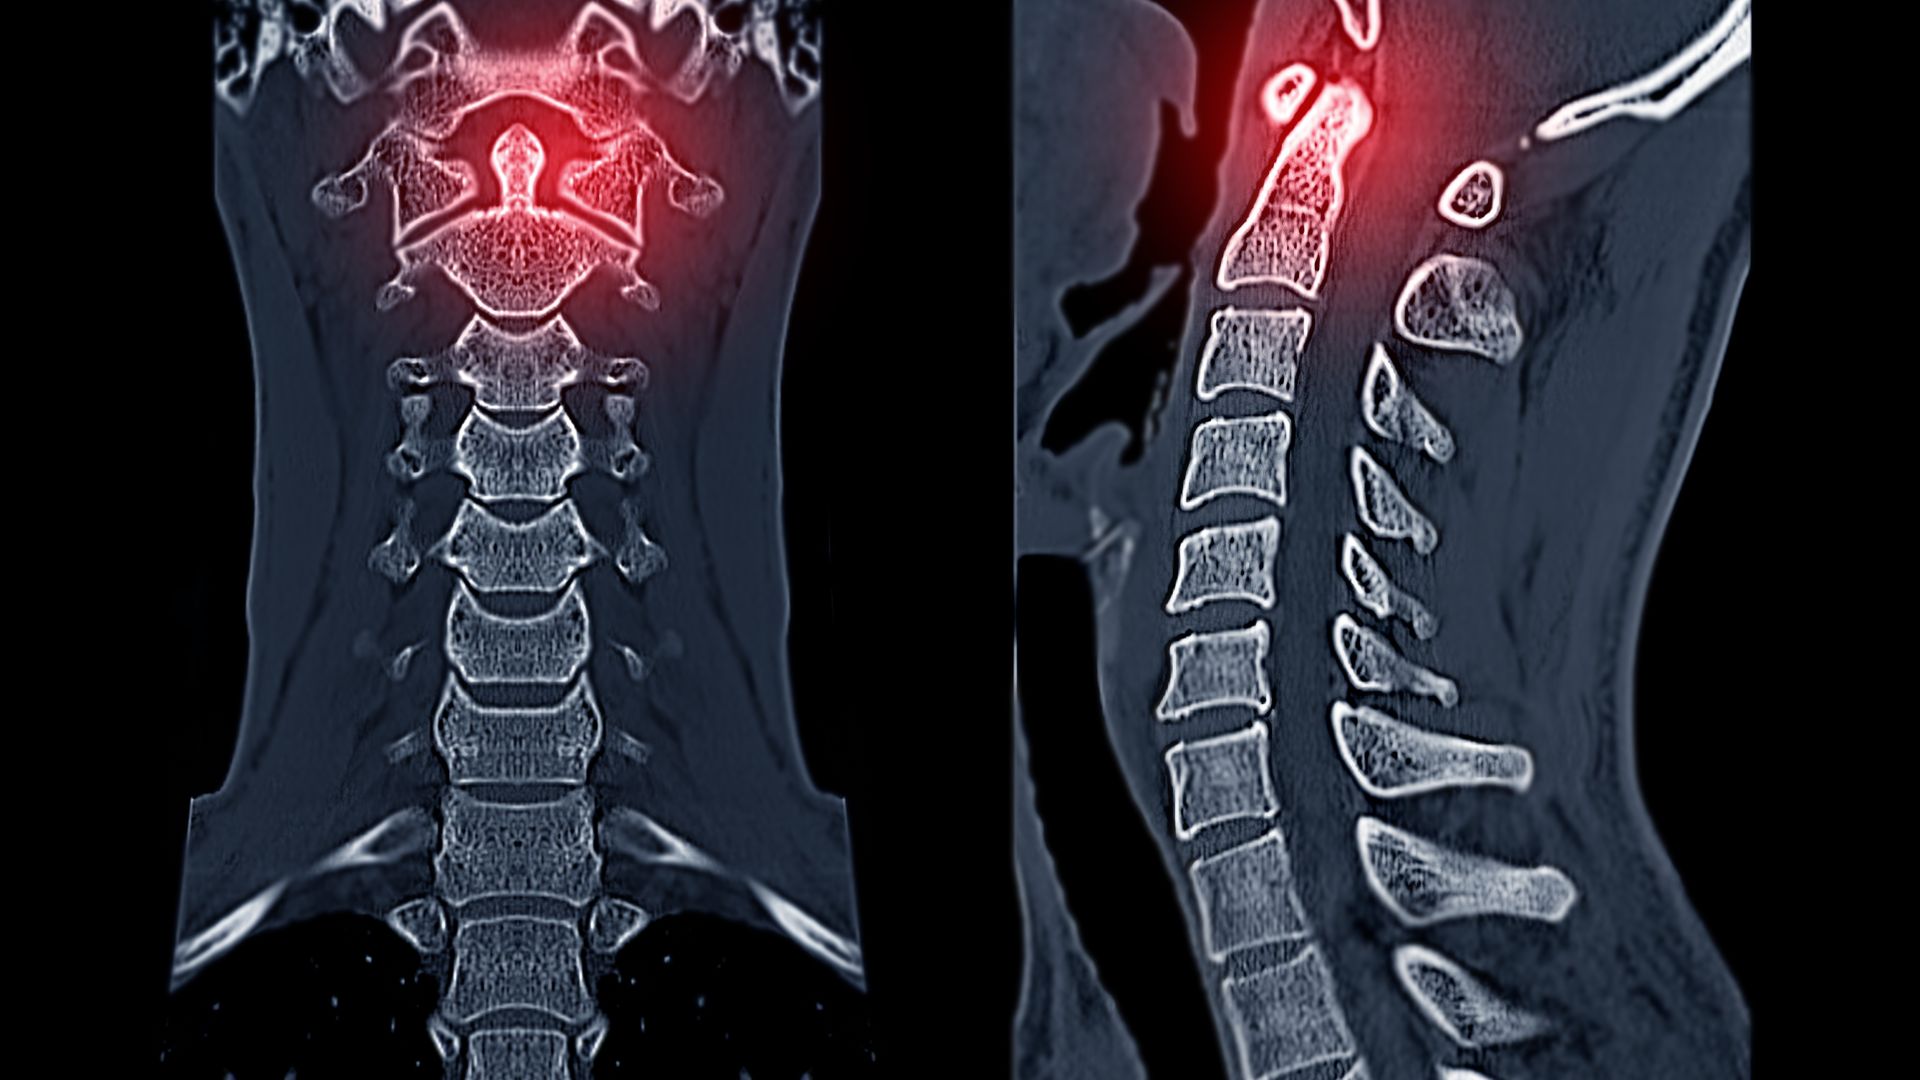

CT Scan cột sống cổ

CT scan cột sống cổ cũng sử dụng tia X nhưng cho hình ảnh chi tiết hơn so với X-quang thường. CT đặc biệt hữu ích trong các trường hợp chấn thương phức tạp, giúp phát hiện các đường gãy nhỏ hoặc tổn thương xương khó quan sát. Tuy vậy, CT có chi phí cao hơn và liều tia X cũng lớn hơn, nên không phải lúc nào cũng được chỉ định ngay từ đầu.

Trong thực hành lâm sàng, X-quang cột sống cổ không thay thế MRI hay CT, mà đóng vai trò như bước sàng lọc ban đầu. Nếu kết quả X-quang bình thường nhưng triệu chứng vẫn kéo dài hoặc có dấu hiệu nghi ngờ tổn thương sâu hơn, bác sĩ có thể chỉ định thêm CT hoặc MRI để đánh giá toàn diện hơn.